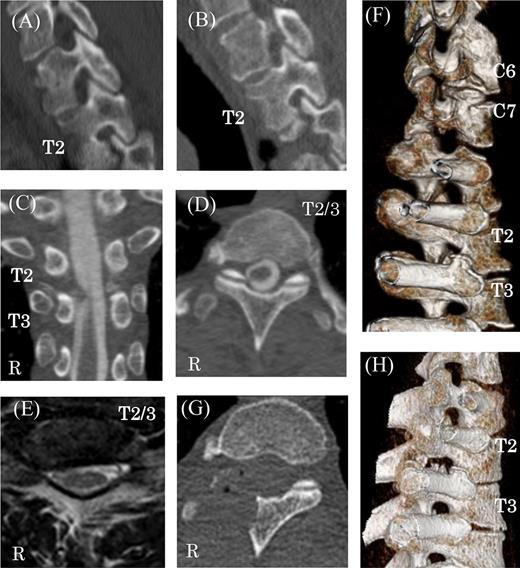

A 60-year-old man presented with 3 months of progressive pain in the right axilla and posteromedial upper extremity. He had undergone C5–6 anterior fusion for cervical spondylosis 5 years prior (Fig. 1B). He had returned to his job as a taxi driver after the anterior fusion. He did not have any traumatic injury or traffic accidents after his anterior fusion. His numerical pain scale rating was 10/10. Examination revealed no sensory disturbance, no abnormal tendon-jerk reflexes and progression of muscle weakness. Cervicothoracic scoliosis had been diagnosed before his anterior cervical fusion (Fig. 1A). Roentgenograms showed scoliosis with a right cervicothoracic curvature with a Cobb angle of 17 degrees before his anterior fusion (Fig. 1A) and 19 degrees on referral to our hospital (Fig. 1B). In addition, computed tomography (CT) scanning revealed bone spurs of the C6–7 facets (Fig. 2F). Magnetic resonance (MR) imaging showed a decrease in intervertebral height, but the nerve root canal was preserved at the C6–7 level. CT images also showed osteophytes of the superior costal facet and articular process at the T2–3 level (Fig. 2B–D). MR images demonstrated a protruded disc at the T2–3 level (Fig. 2E and F).

Preoperative and postoperative CT and MR images. (A) Thoracic sagittal views of CT image before cervical anterior fusion at right T2 nerve root canals. Preoperative multi-planar CT images (B–D) and reconstructed 3D images showing right C6–7 and T2–3 nerve root canal stenosis caused by bone spurs of facets and vertebral bodies (F and H). MR imaging of protruded disks at the T2–3 level (E). Postoperative CT shows the decompression of the right T2–3 thoracic nerve root canal (G).

The width and height of the nerve root canal on the right measured 6.4 mm and 4.2 mm at C7 and 5.2 mm and 5.1 mm at T2, respectively [1]. The right C7 and T2 nerve root canals were narrow compared to left side (left C7 width 8.0 mm, height 8.2 mm; left T2 width 9.9 mm, height 10.5 mm). From C5−T4, mean width was 9.4 ± 1.8 mm and mean height was 9.2 ± 2.4 mm. Before anterior cervical fusion, the width and height of the nerve root canal on the right at T2 had been 7.4 mm and 5.0 mm and on the left had been 8.6 mm and 12.2 mm, respectively (Fig. 2A). These findings indicate that the nerve root canals on the right at C7 and T2 were degenerative.

We performed right T2–3 hemilaminectomy and partial facet resection. After the surgery, his symptoms were remarkably improved. Postoperative CT imaging showed decompression of the T2–3 thoracic nerve root canal (Fig. 2G and H). Six months later, his pain had completely disappeared.